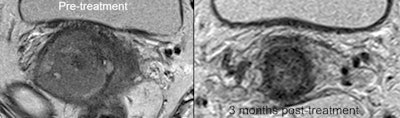

40-year-old LACC patient with stage B disease, node negative. Indeterminate residual T2-weighted signal change post CRT -- grade 3 (moderate response).

40-year-old LACC patient with stage B disease, node negative. Indeterminate residual T2-weighted signal change post CRT -- grade 3 (moderate response). Indeterminate residual T2-weighted signal change post CRT -- grade 3. No corresponding residual metabolic activity on PET/CT -- grade 1 (complete metabolic response). Patient remains disease-free three years later.

Indeterminate residual T2-weighted signal change post CRT -- grade 3. No corresponding residual metabolic activity on PET/CT -- grade 1 (complete metabolic response). Patient remains disease-free three years later."Our current work is focused on evaluating whether extracting novel (quantitative) features -- including metabolic tumour volume and standardized uptake value metrics derived from FDG-PET/CT as well as radiomic features along with quantitative feature analysis of MRI -- has a greater ability to predict patient outcome when compared to qualitative analysis," he told AuntMinnieEurope.com.